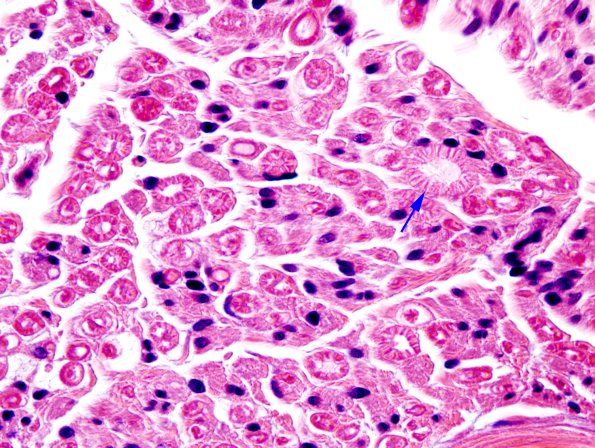

The endoneurial content of individual axons are better seen in this fascicle compared to the majority of biopsies because the myelin sheaths exhibit a neurokeratin or “wagon-wheel” artifact (arrow).. A typical formalin fixed paraffin embedded H&E-stained nerve provides a limited amount of information in the analysis of individual axons. (H&E)